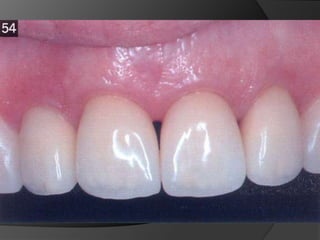

CORONA TOTALMENTE CERÁMICA: Combinación de recubrimiento completo y máxima estética. La eliminación de estructura dentaria es mayor.

CARILLAS EN CERÁMICA: Alternativa menos agresiva cuando lo que se busca es el cambio de color o de forma en la superficie vestibular

CORONA TOTALMENTE CERÁMICA:Combinación de recubrimiento completo y máxima estética. La eliminación de estructura dentaria es mayor.

CARILLAS EN CERÁMICA:Alternativa menos agresiva cuando lo que se busca es el cambio de color o de forma en la superficie vestibular